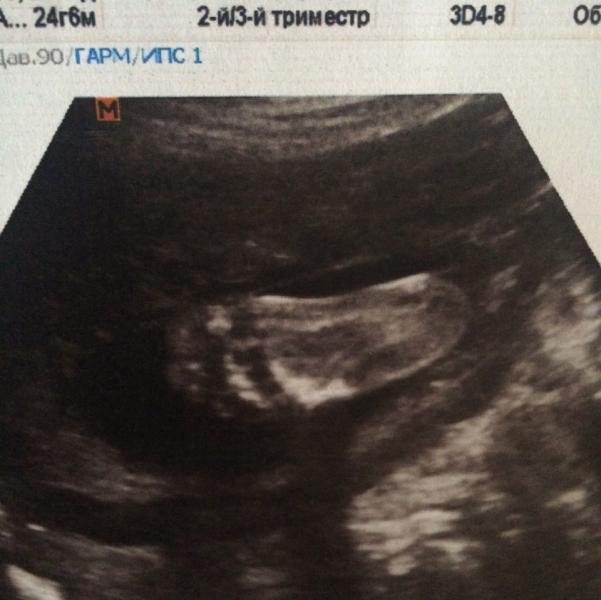

Ходили вчера на УЗИ в ЦИР на Дубровке к Нагоевой! Все очень понравилось! Смотрела долго, делала все измерения.. Все комментировала, очень мило и с пониманием ☺️ смеялись вместе над причудами в животике малышки! В общем с УЗИ в жк не сравнить! Где просто молча все проходит и ты даже ничего не видишь.. Надавала кучу фото, хоть и малышня все время закрывалась и пряталась, немного все таки удалось сделать)) девочки, такой вопрос! Нужно ли уже на моем сроке трансвагинальное УЗИ? Нагоева сказала что мо...